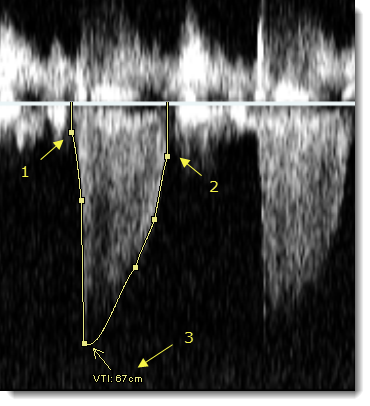

- Για να τοποθετήσετε την πρώτη λαβή της καμπύλης ταχύτητας, κάντε κλικ στο σημείο έναρξης (1) για τη μέτρηση στην περιοχή Doppler της εικόνας υπερηχογραφήματος.

- Για να τοποθετήσετε επιπλέον λαβές, κάντε κλικ για να εντοπίσετε την οπτικοποίηση του παλμού και να ορίσετε με ακρίβεια την καμπύλη της ταχύτητας.

- Για να ολοκληρώσετε την καμπύλη, κάντε διπλό κλικ για να τοποθετήσετε την τελευταία λαβή (2).

Το VTI υπολογίζεται και εμφανίζεται σε εκατοστά (3).